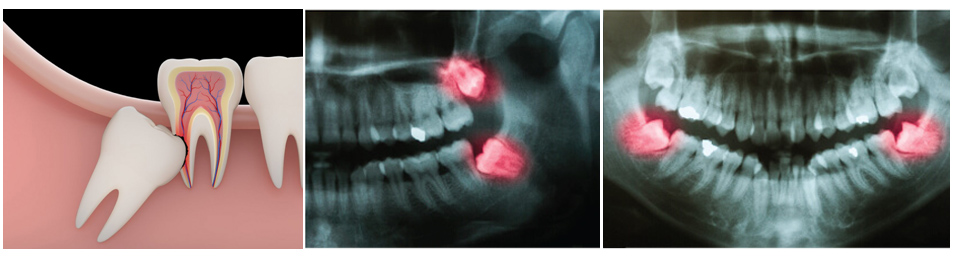

ฟันคุด คือ ฟันที่ไม่สามารถขึ้นได้เต็มที่ตามปกติ โดยมากมักจะเป็นในฟันกรามซี่สุดท้าย สามารถพบได้ทั้งฟันบน และฟันล่าง แต่ส่วนมากฟันล่างจะมีโอกาสพบว่าเป็นฟันคุดได้มากกว่า

ความยากง่ายในการผ่าเอาฟันคุดออก จะขึ้นอยู่กับตำแหน่งของฟันว่าเป็นการฝังลึกลงไปในกระดูกมากน้อยแค่ไหน และมีความเอียงมากแค่ไหน หรือนอนตะแคงเลย และถ้าฟันคุดยิ่งฝังลึกลงไปมาก หรือมีความเอียงมากก็จะยิ่งทำได้ยาก

• ทันตแพทย์จะทำการเอ็กซเรย์เพื่อดูฟันคุด และดูโครงสร้างกระดูกบริเวณรอบๆของฟันคุดซี่ที่จะทำการเอาออก